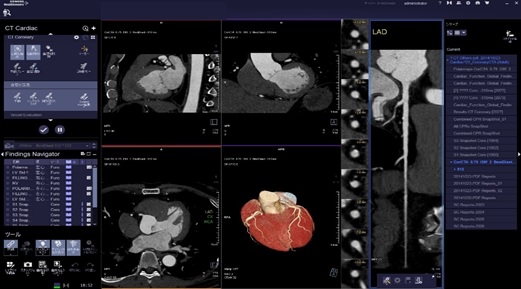

当院の装置は管球1回転最速0.28秒と非常に早く、幅広い心拍の方に対応しています。

解析処理は専門のワークステーションを使用し、読影は循環器内科医師と画像診断専門医(遠隔画像診断支援)双方で行い、結果を循環器内科医師よりお伝えしています。